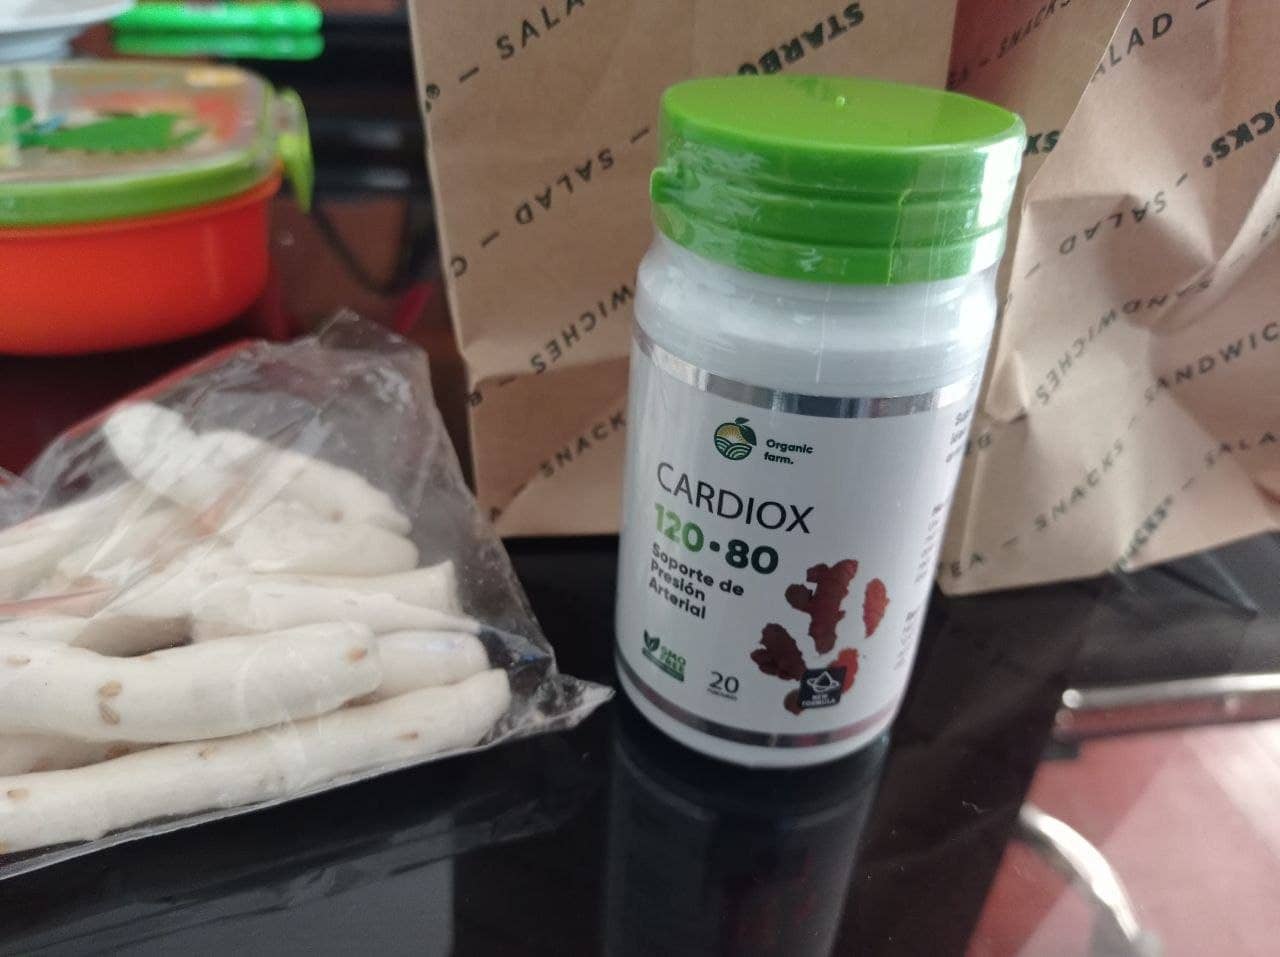

Para una limpieza segura de los vasos, recomiendo un producto con una reputación impecable: el nutracéutico Cardiox. Cardiox puede potencialmente extender la vida de 11 a 17 años, infundiendo energía y vigor en lugar de drenar vitalidad.

Es incluso más seguro que una infusión. En términos de efectividad, solo es superado por la limpieza quirúrgica de los vasos. Sin embargo, a diferencia de la cirugía, no tiene complicaciones ni efectos secundarios. En solo un curso, limpia todos los vasos del cuerpo, desde las grandes arterias hasta los delicados capilares.

Cardiox es una mezcla en cápsulas de extractos de plantas. Al mezclarse con agua, estos compuestos se activan. Estos agentes ayudan a despejar los vasos del colesterol, coágulos (placas de calcio) y restos de medicamentos, asegurando un flujo sanguíneo suave.

Las toxinas acumuladas que han afectado tu bienestar durante años pueden eliminarse con Cardiox en solo 1.5 a 2 meses de uso constante.

En un mes y medio, Cardiox disuelve y elimina 4 kg de placas de colesterol, reduce entre 900 gramos y 1 kg de masa trombótica, y elimina 350-400 gramos de cristales de calcio.